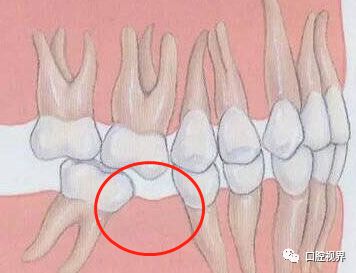

牙齿病变

所谓得了灰指甲,一个传染两。

只要有一颗牙齿出现龋坏现象,就很可能影响到相邻的牙齿,从而使得两颗牙之间形成间隙。